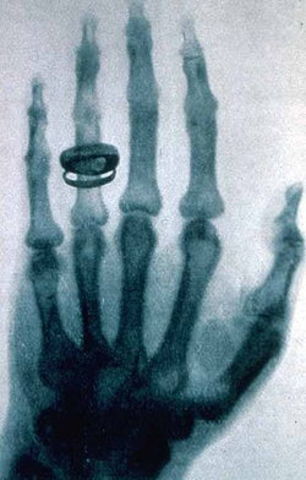

Fueron descubiertos por Wilhelm Röntgen, y hoy en día son necesarios para detectar enfermedades óseas y de los tejidos blandos. (http://monicadelcerro.blogspot.com.co/2014/04/top-ten-de-los-grandes-descubrimientos.html)